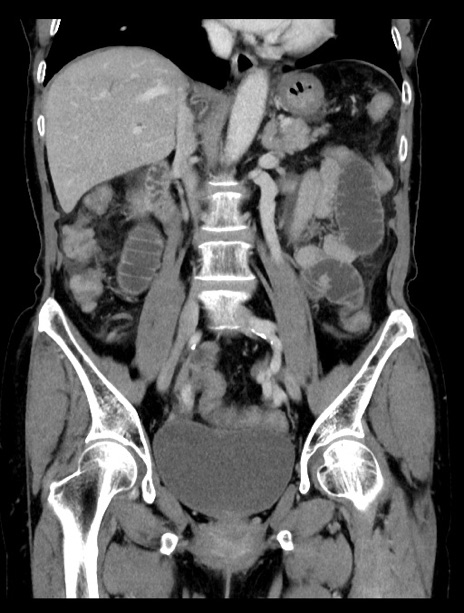

症例23(冠状断像)

【症例】70歳代女性

【主訴】下腹部痛・嘔吐

【現病歴】2日前より腹痛あり。昨日嘔吐あり。症状改善しないため来院。

【既往歴】胃GISTに対して胃部分切除後。

【身体所見】BT 37.1℃、BP 128/77mmHg、腹部:平坦・軟、下腹部に圧痛あり。

【データ】WBC 10200、CRP 0.31